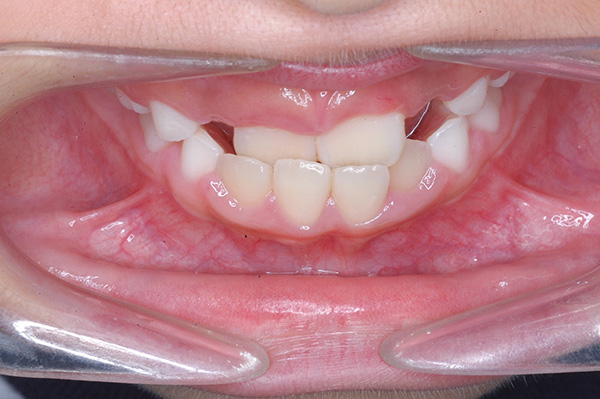

主訴 反対咬合 診断名 前歯部反対咬合

口腔内所見 over jet -2.5mm、over bite 2.0mm、大臼歯関係はⅠ級 。Hellmanのdental ageはⅡCであり前歯部は反対咬合を呈していた。

顔貌所見 正貌はほぼ左右対称。側貌はconvex typeでありNasolabial Angleは鋭角であった。

家族歴や側貌所見、下顎は大きいもののANBは2°でSellaに対して下顎頭は後方に位置していることなどから将来的に重度な下顎前突へ移行することは少ないと予測できた。